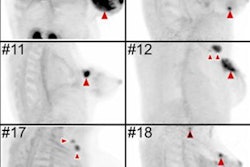

PET scans were performed 60 minutes after administration of 150-250 MBq of Ga-68-labeled FAP-specific tracers. CT scans for TNM staging were performed an average of 17.6 days before FAP-specific PET/CT (Biograph mCT Flow, Siemens Healthineers).

The researchers found that Ga-68-FAPI-PET/CT provided new TNM findings for 10 of 19 PDAC patients (53%), which included the upstaging of eight of 12 patients (67%) with recurrent or progressive disease, while one patient's (8%) recurrent or progressive cancer was downgraded. Among seven PADC patients with primary disease, one case out of seven (14%) was upstaged; no patients were downstaged.

Contrast-enhanced CT (ceCT) and FAPI-PET/CT (68Ga-FAPI-PET) images from the same patient with local disease recurrence. In contrast to CT, FAPI-PET/CT discriminates a metastatic lymph node from the local recurrence mass (red arrow). FAPI-PET/CT also reveals possible new liver (yellow arrows) and bone (blue arrows) metastases. Images courtesy of Journal of Nuclear Medicine."In all cases, changes in staging were caused by the detection of new or additional distant metastases in one or more organ systems," the authors added. They also found a "markedly elevated uptake" of Ga-68-FAPI in most PDAC patients as soon as one hour after administration.